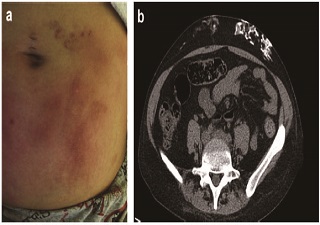

【答案公布】腹部皮下钙化结节、重度高磷血症